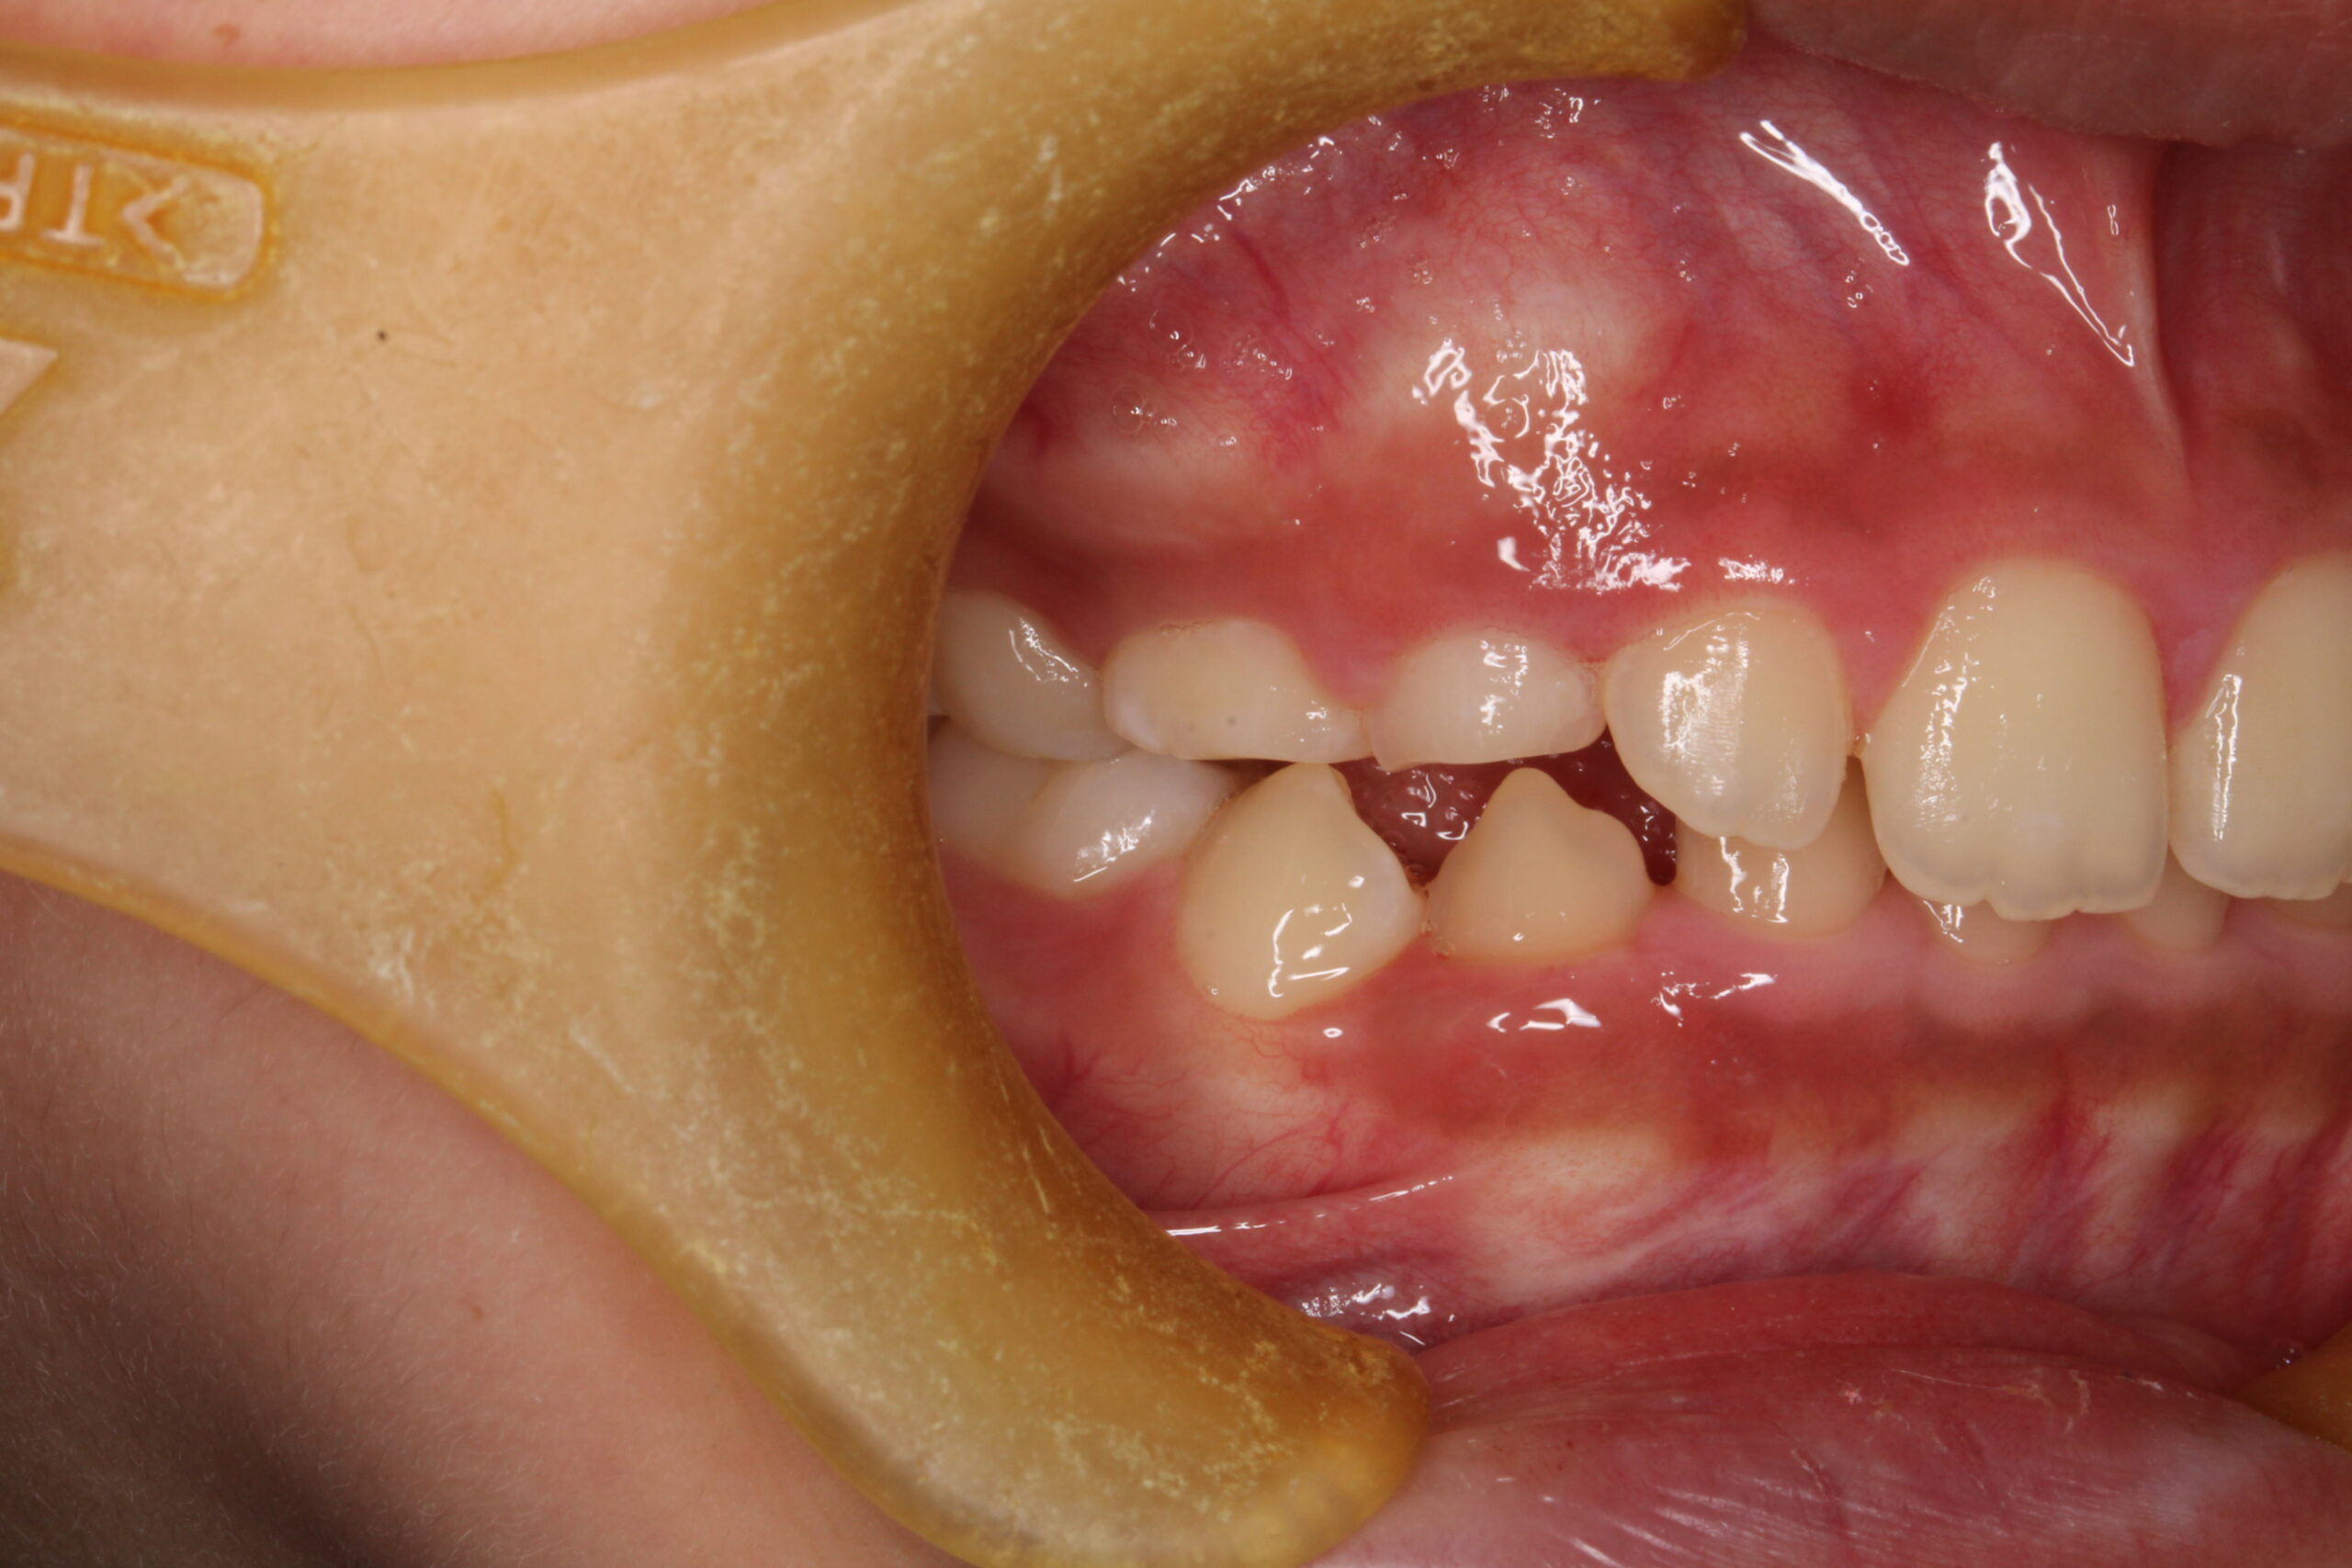

矯正術前:前歯部あおり

矯正術後:前歯部あおり